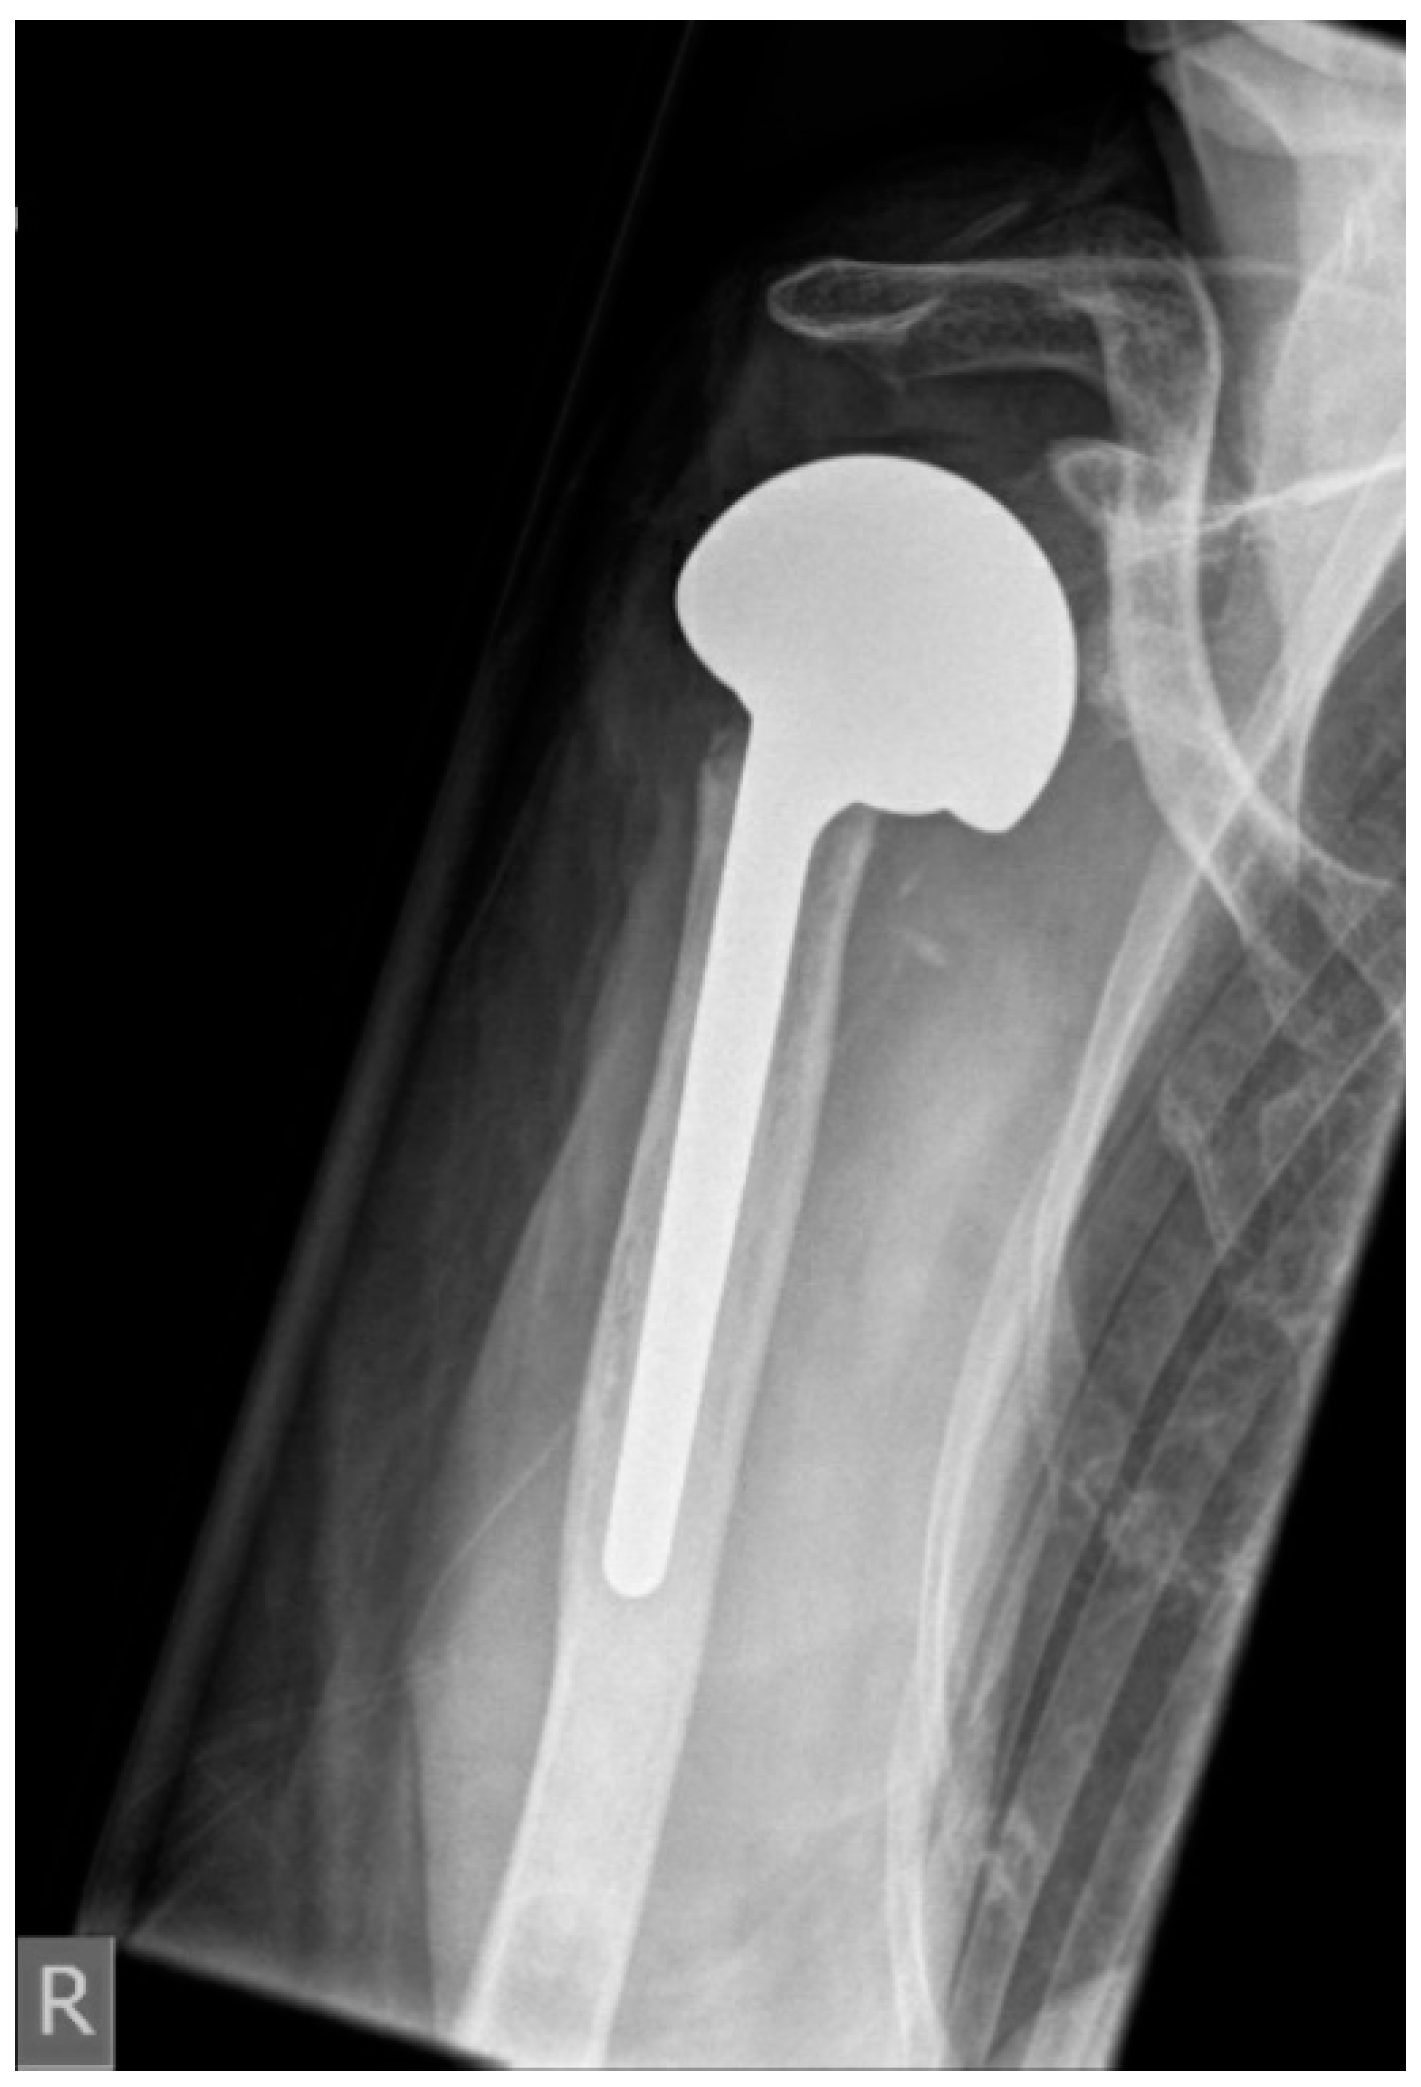

| Hemiprothesis after fracture (n) | 7 |

| Reimplanted prostheses | |

| RSA (n) | 9 (56%) |

| HA with CTA head (n) | 3 (19%) |

| Reverse proximal humeral replacement (n) | 4 (25%) |